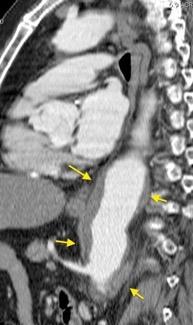

Aneurisma aórtico intracrural

/Restrepo CS et al. The diaphragmatic crura and retrocrural space: normal imaging appearance, variants, and pathologic conditions. Radiographics 2008